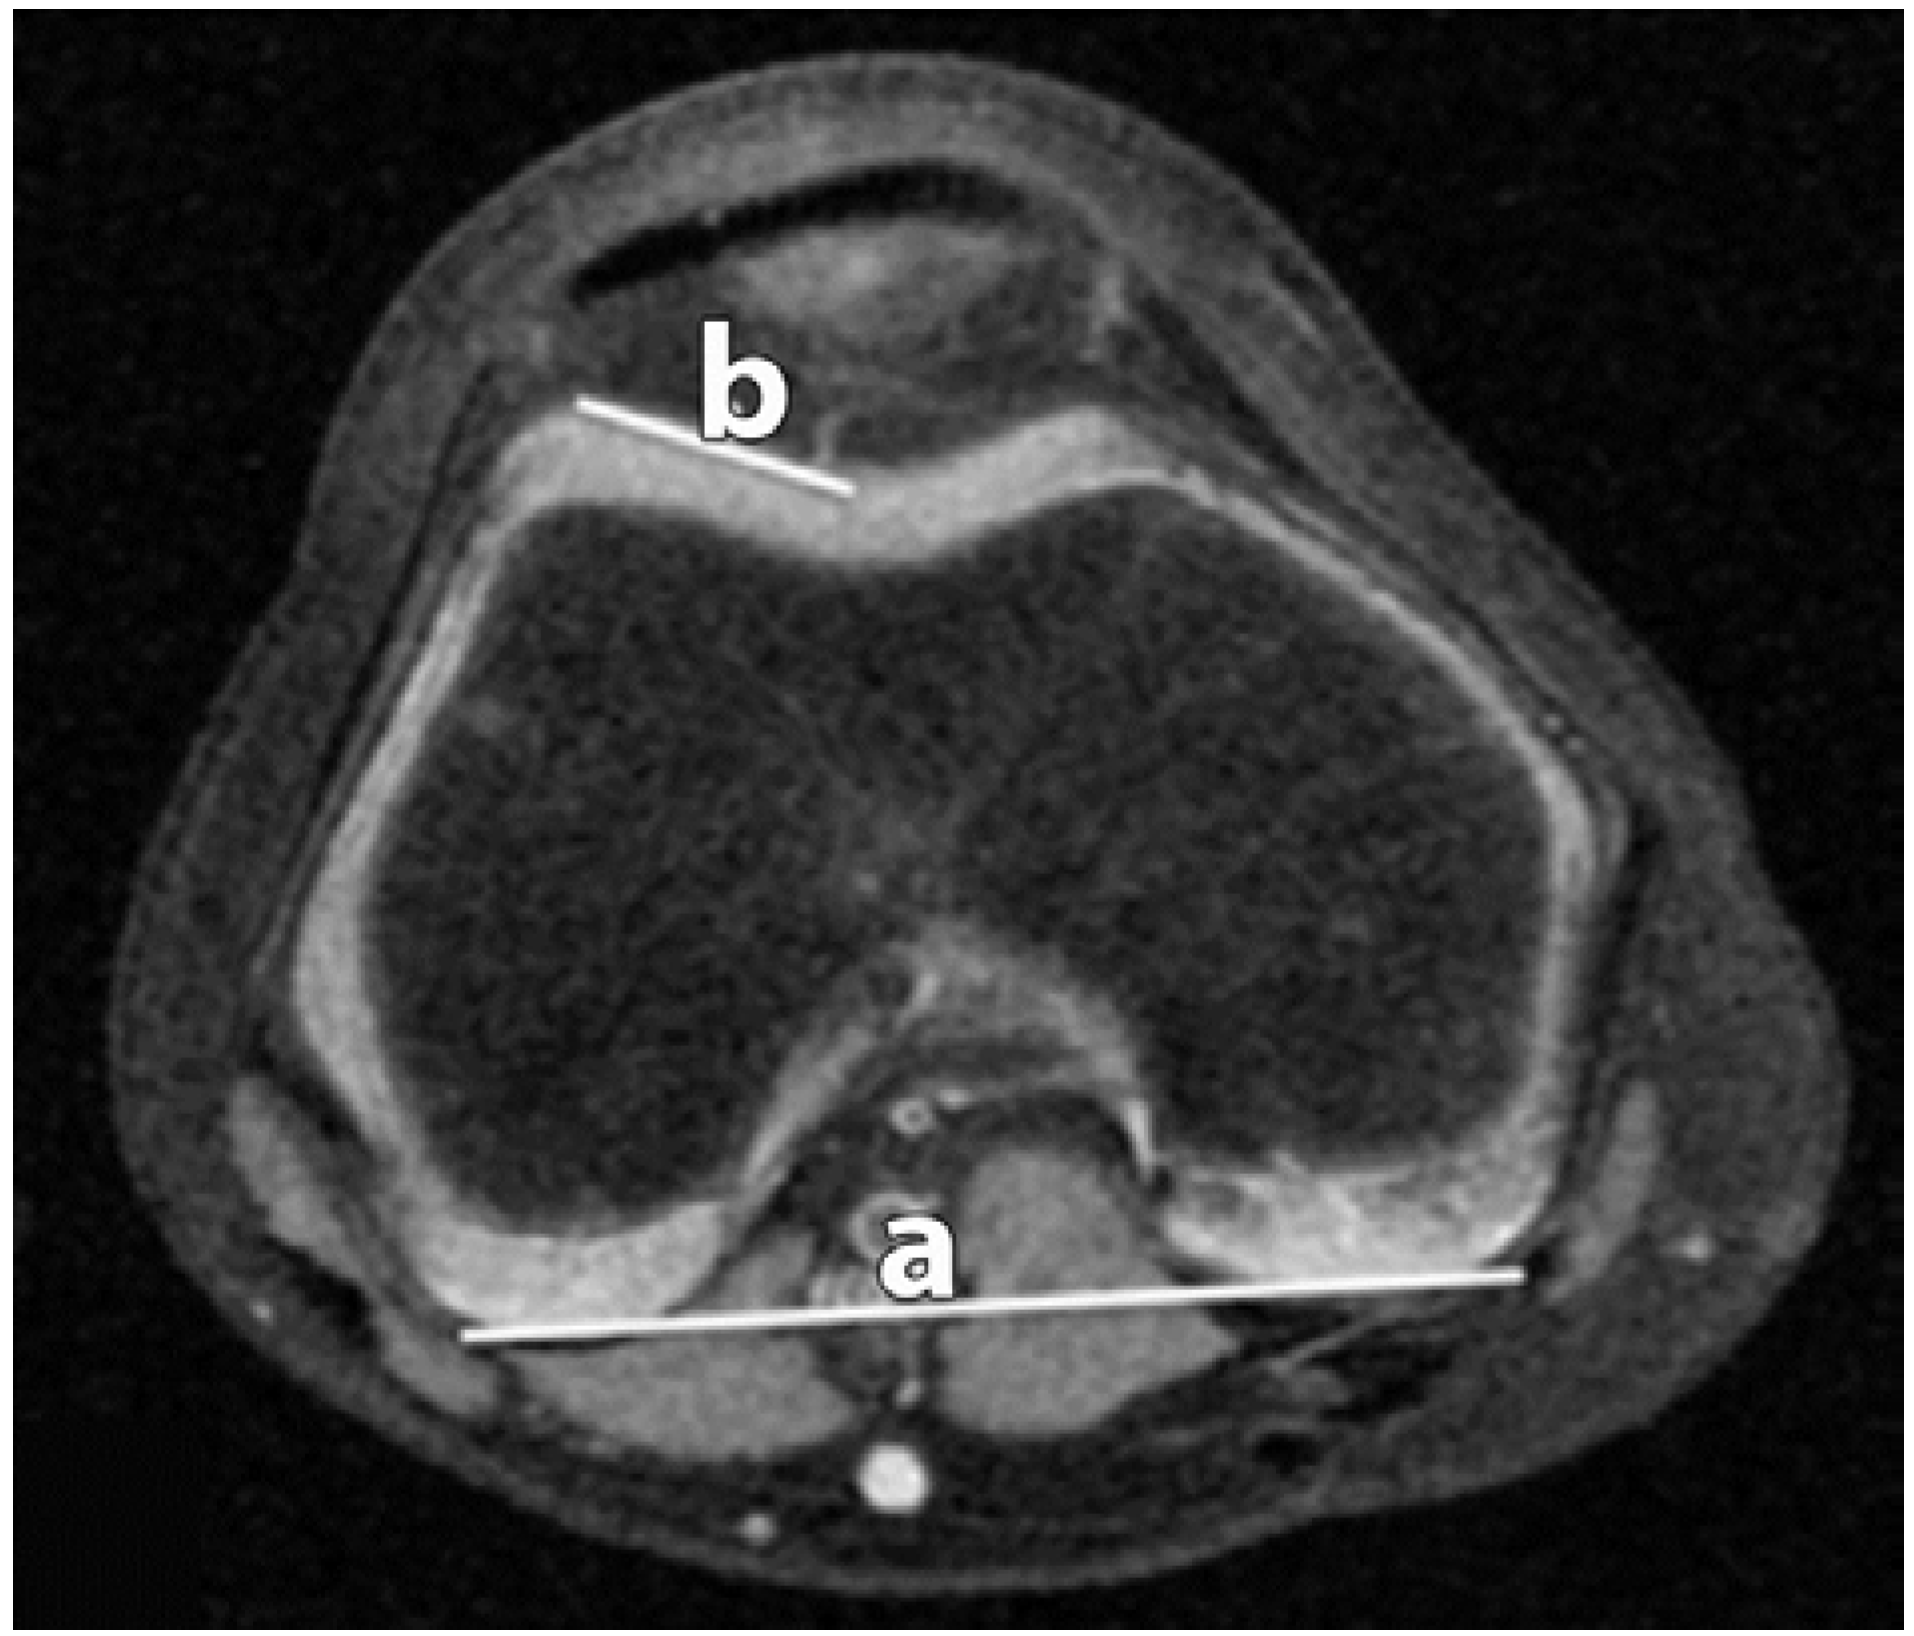

Figure 1.

Lateral Trochlear Inclination (LTI). The angle between the lateral trochlear facet (b); and the line along the posterior condyles (a) is measured.

Figure 2.

Trochlear Facet Asymmetry (TFA). The distances of the lateral facet (b); and medial facet (a) are recorded.